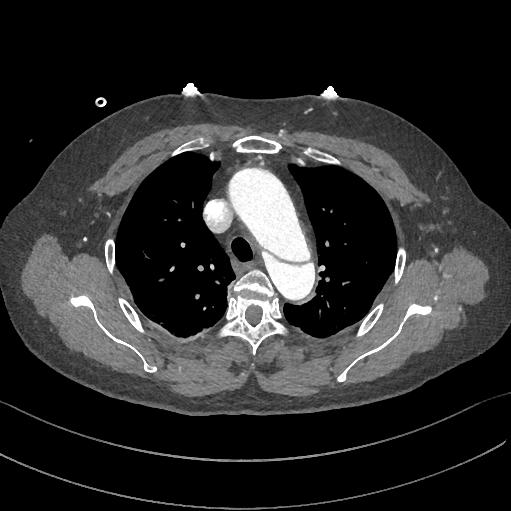

下图的胸部CT平扫,有什么大问题?

图4

仔细一看,主动脉里面有线样高密度阴影!这个要高度警惕主动脉夹层!

图5